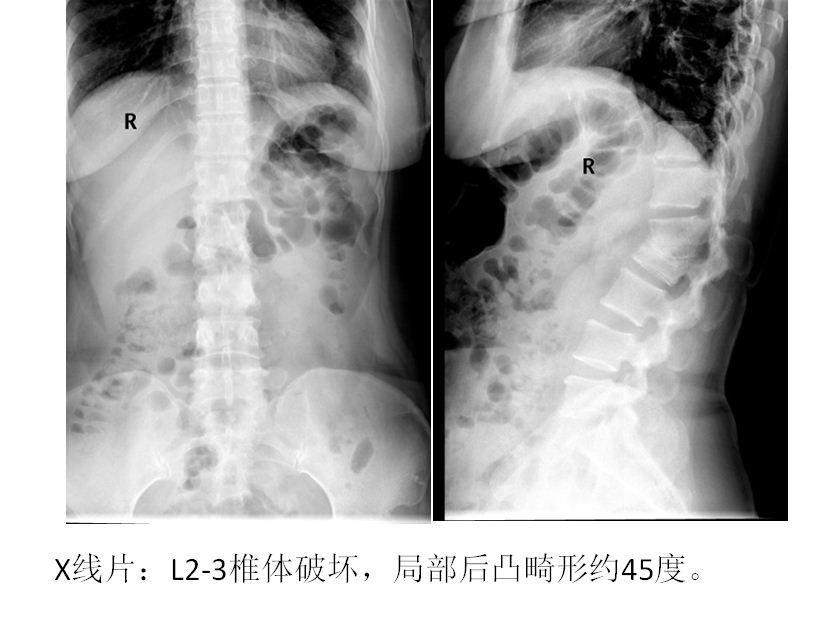

脊柱结核并后凸畸形

图片尺寸414x828

脊柱结核病例25:一例陈旧性脊柱结核伴后凸畸形的治疗 - 好大夫在线

图片尺寸837x628